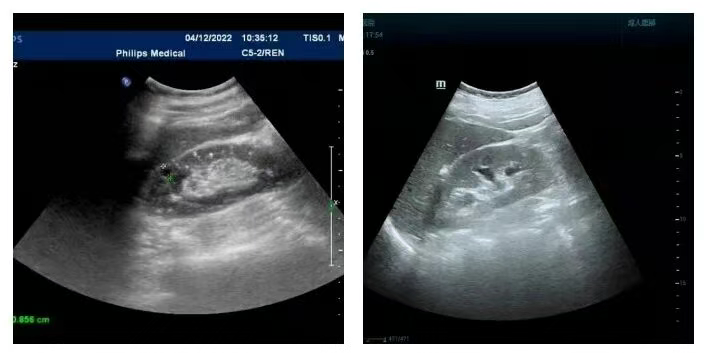

3.前列腺钙化、纤维化

是前列腺发生炎症愈合后留下的疤痕,是前列腺结石的前兆。前列腺结石常伴有慢性前列腺炎,一般通过彩超检查能看到这些病变。由于前列腺结构特殊性,发生钙化、结石一般没有较好的治疗方法。

前列腺钙化(纤维化)、结石上会滋生细菌,所以又是前列腺炎反复发作的一个原因,不能忽视。前列腺中的钙化点多为前列腺慢性炎症引起的钙化或者前列腺结石,一般不会有什么症状,也无需治疗。